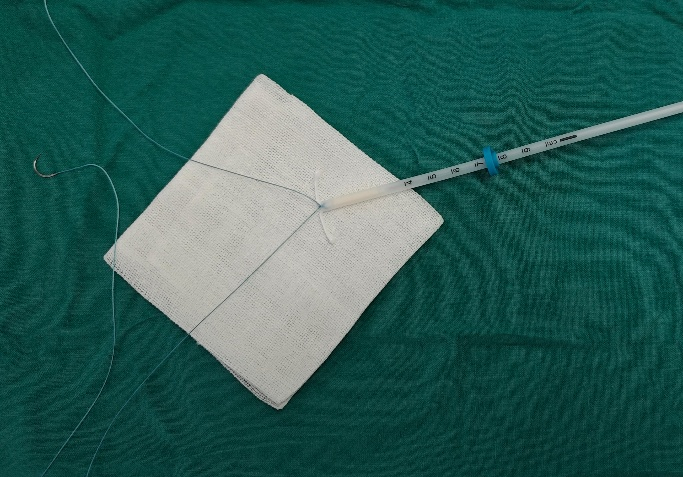

将缝线中间部位与曼月乐环横臂与纵臂交界处3-4个结即可,注意打结要牢靠。打结时不建议将曼月乐环从推进杆中取出,用推进杆上环不仅可以尽量遵守无菌原则,而且更加容易(图6)

prolene缝线 打结时为什么要喷水曼月乐环总掉?缝合固定术的“10个关键技巧”全公开!从缝线选针到打结,手把手教学_https://www.jmylbn.com_新闻资讯_第6张

图6